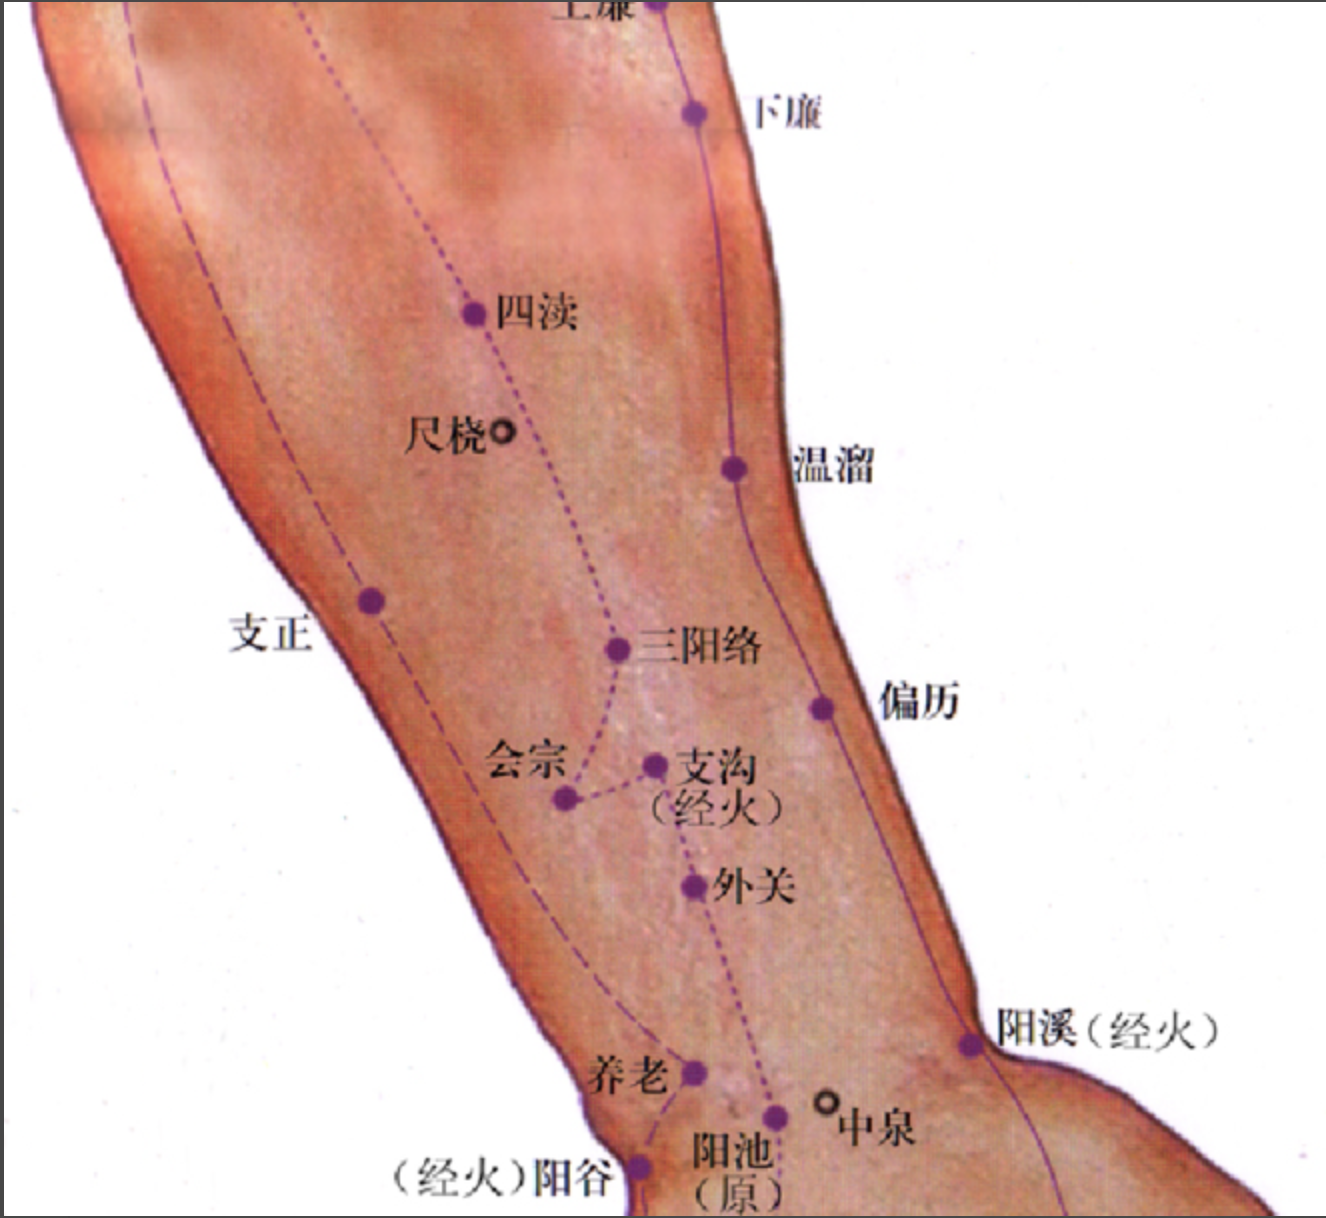

【(十)手少阳三焦经(图10-28)】

2、歌诀 二十三穴手少阳,关冲液门中渚旁。阳池外关支沟正,会宗三阳四渎长。天井清冷渊消泺(luò),臑会肩髎天髎堂。天牖(yǒu)翳风瘛(chì)脉青,颅息角孙丝竹空。和髎耳门听有常。

3、经脉循行 起于无名指末端(关冲)上行于第 4、5掌骨间,沿腕背、出于前臂外侧尺桡骨之间,经肘尖沿上臂外侧达肩部,交大椎,再向前入缺盆部,分布于胸中,络心包,过膈,从胸至腹,属于上、中、下三焦。

胸中支脉:从胸向上出于缺盆部,上走项部,沿耳后直上至额角,再下行经面颊部至目眶下。

耳部支脉:从耳后入耳中,出耳前,与前脉交叉于面颊部,到目外眦,与足少阳胆经相接。

4、主要病候 腹胀、水肿、遗尿、小便不利、耳聋、咽喉肿痛、目赤肿痛、颊肿、耳后、肩臂肘外侧痛等。

5、主治概要 主治侧头、耳、目、胸胁、咽喉病、热病及经脉循行部位的其他病证。

关冲

【附注】 三焦经井穴。

中渚(zhǔ)

【附注】 三焦经腧穴。

外关

【附注】 三焦经络穴,八脉交会穴之一,通阳维脉。

支沟

【附注】 三焦经络穴。